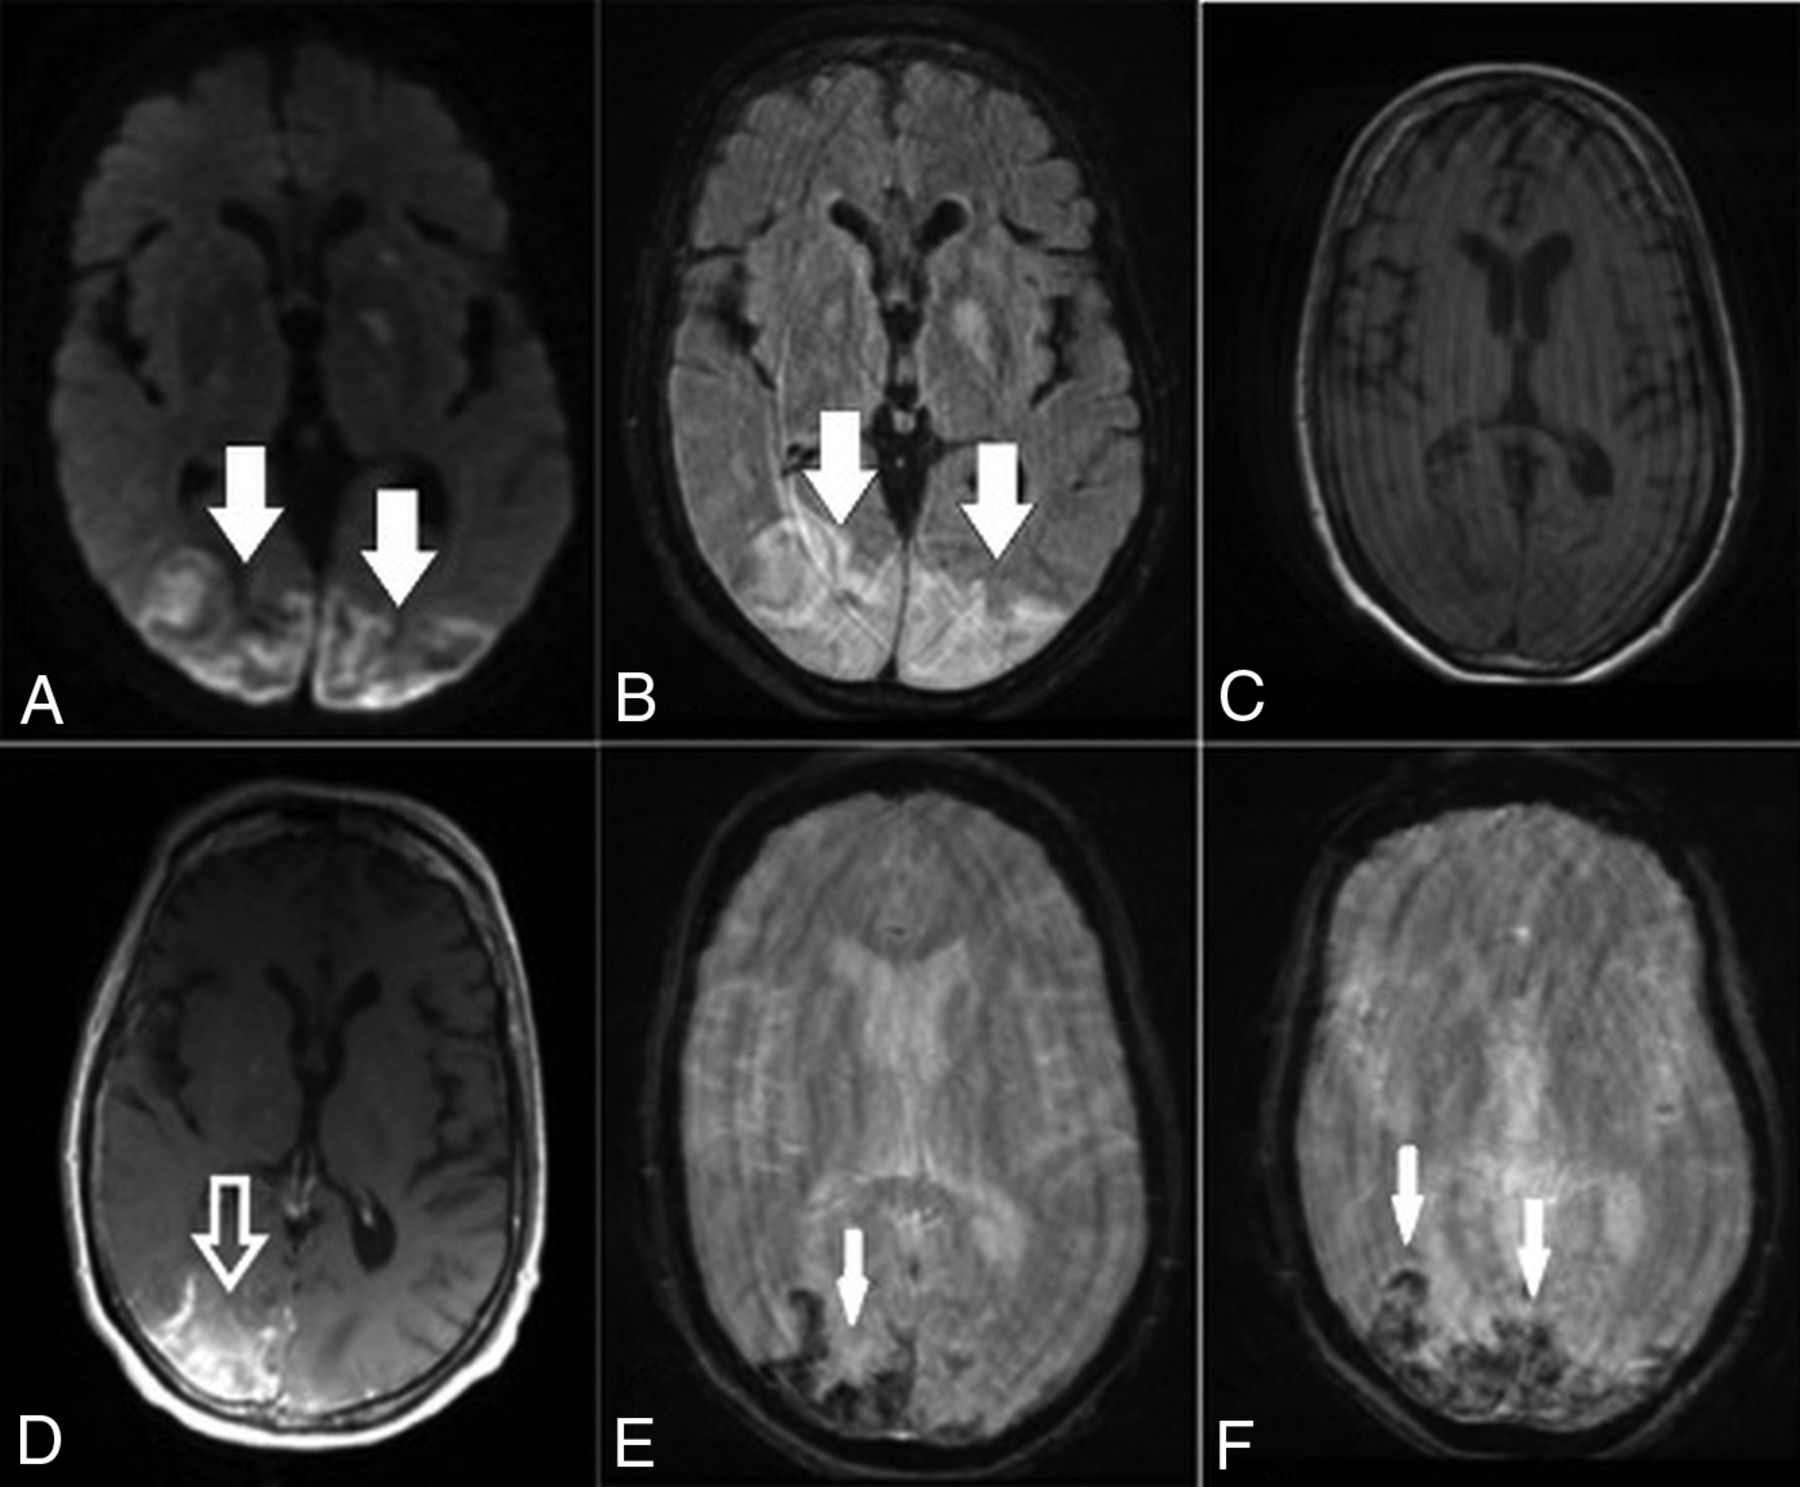

On March 25, she developed altered mental status, including lethargy and confusion, and was transferred to our hospital. In the emergency department, the patient was afebrile, with laboratory values notable for Cr = 1.65, blood urea nitrogen = 23, lactate = 2.3, and mild hyponatremia. Arterial blood gases were normal, and she denied cough, chest pain, and shortness of breath. The patient had variations in blood pressure, ranging from 115/72 to 178/83 mm Hg at admission. Chest CT demonstrated bilateral multifocal ground-glass opacities concerning for COVID-19 pneumonia due to its high prevalence in the region. Findings of a polymerase chain reaction test were positive for SARS-CoV-2 on March 27. Noncontrast head CT demonstrated edema in the bilateral parieto-occipital regions with associated mass effect and cortical sulcal effacement (Fig 3). MR imaging of the brain performed on March 27 revealed multiple areas of restricted diffusion with associated edema, most extensive in the posterior parieto-occipital lobes but also in the right frontal lobe, basal ganglia, and cerebellar hemispheres. The SWI sequence demonstrated extensive superimposed hemorrhages in the parieto-occipital region along with abnormal enhancement (Fig 4). Findings of concurrently performed MR angiography of the head and neck were unremarkable: Specifically, evaluation of the posterior circulation demonstrated a patent vertebrobasilar system. The patient remained afebrile with normal respiratory status, including oxygen saturation; after gradual improvement in her mental status, she was discharged.

Axial noncontrast CT images demonstrate vasogenic/cytotoxic edema in the parieto-occipital regions suggestive of PRES (arrows).